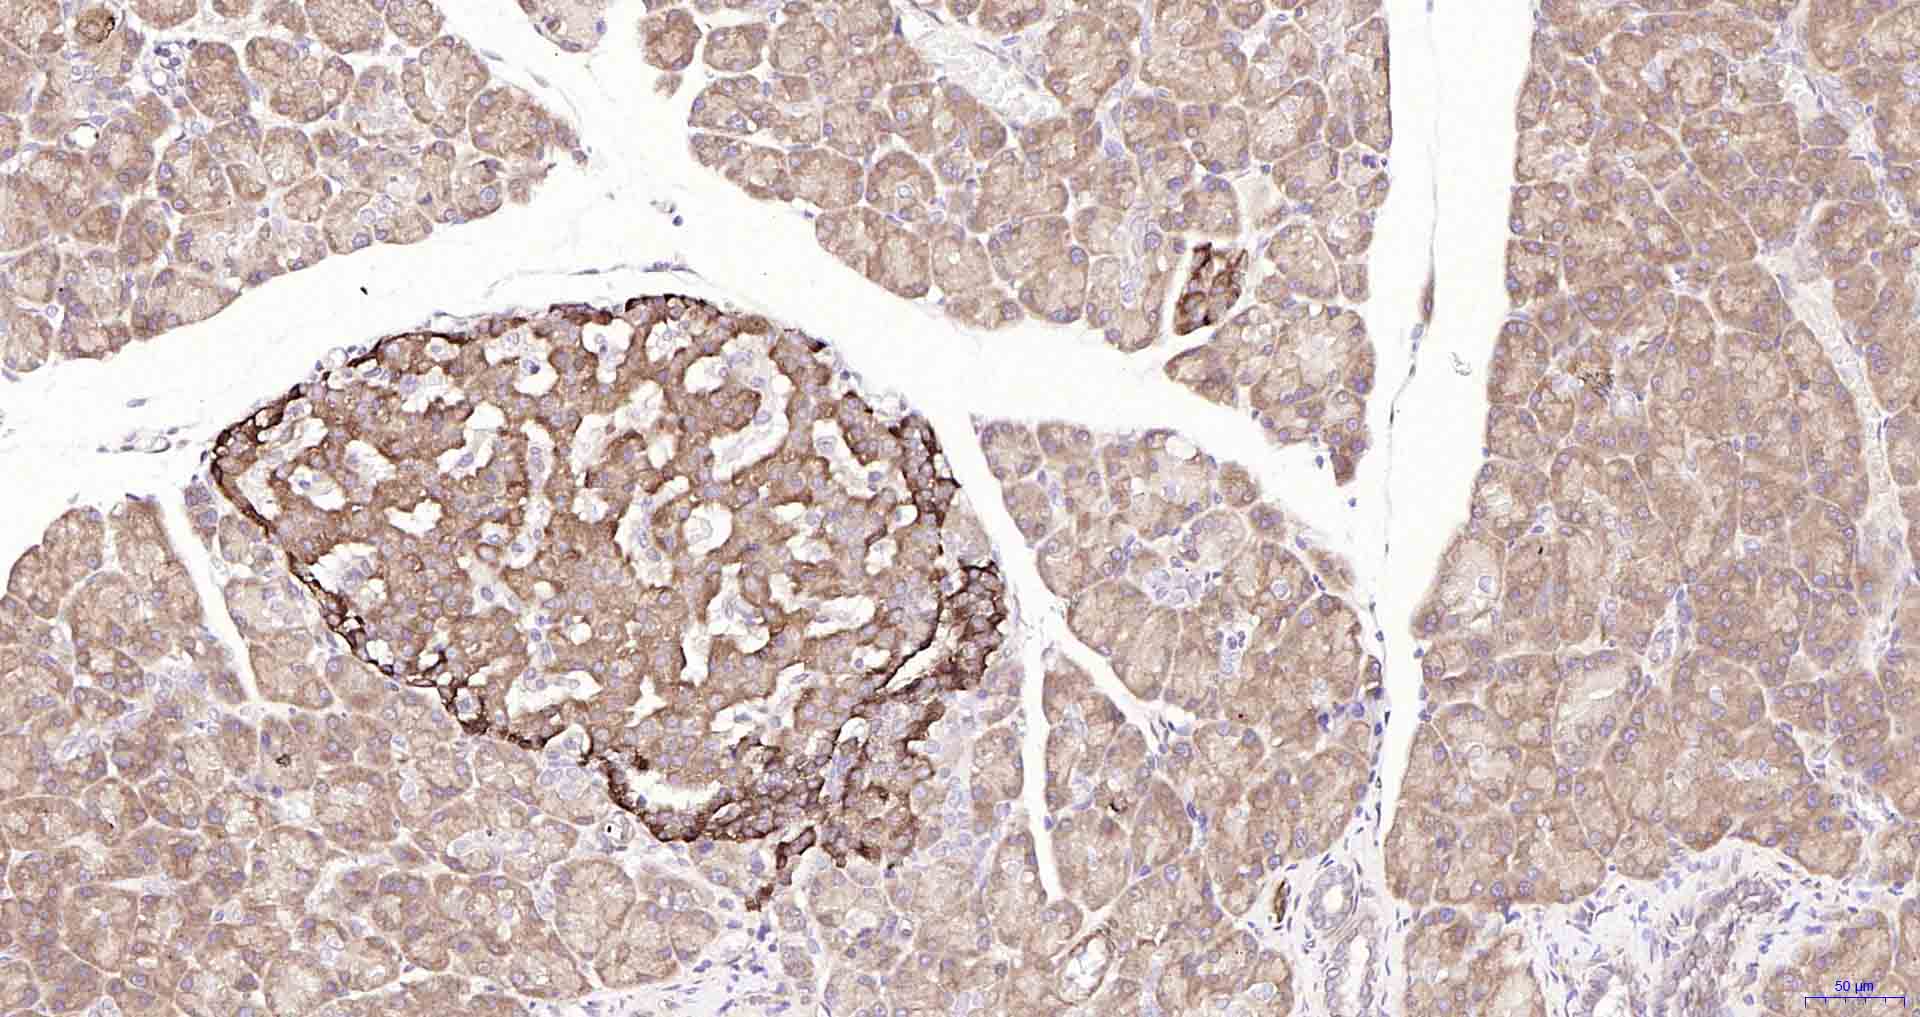

Paraformaldehyde-fixed, paraffin embedded Mouse Pancreas; Antigen retrieval by boiling in sodium citrate buffer (pH6.0) for 15 min; Antibody incubation with ULK1 Monoclonal Antibody, Unconjugated(bsm-61039R) at 1:100 overnight at 4°C, followed by conjugation to the SP Kit(Rabbit, SP-0023) and DAB (C-0010) staining.